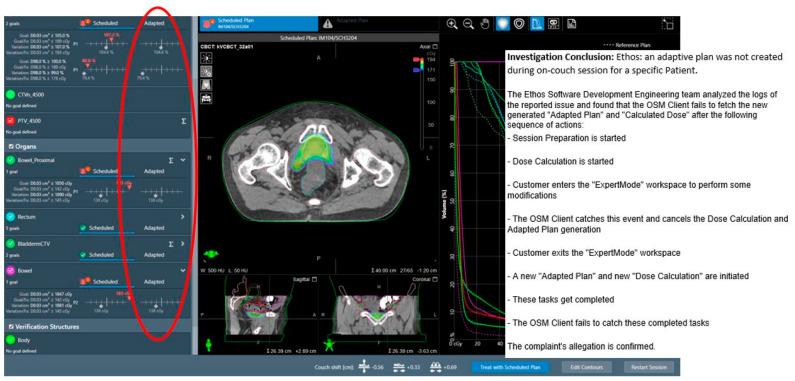

Cone-beam computed tomography (CBCT)-guided online adaptive radiotherapy (oART) represents a significant advancement in radiation oncology, enabling on-couch plan adaptation to account for daily anatomical changes. While this automation improves precision and workflow efficiency, it also introduces new failure modes (FMs) and workflow irregularities. This study aimed to systematically evaluate the clinical and technical challenges associated with CBCT-guided oART implementation. We retrospectively analyzed over 1000 CBCT-guided oART sessions for pelvic malignancies performed at our institution. A multidisciplinary team conducted a comprehensive review to identify and classify FMs, followed by root cause analysis (RCA) to evaluate their impact on treatment safety, efficacy, and workflow robustness. In addition to session-terminating FMs, we identified recurring failure modes across three major domains: (1) system-driven issues, such as rigid target localization and software-driven irregularities; (2) patient-driven challenges, including interfractional and intrafractional anatomical variations; and (3) treatment planning and execution failures, including excessive dose hotspots from field-of-view limitations. The system's closed-loop automation, while streamlining processes, introduced rigid constraints in plan adaptation and fallback plan execution, occasionally leading to unintended dose discrepancies. This study provides a comprehensive clinical practice-based evaluation of CBCT-guided oART, highlighting system-specific failure modes and their implications. Addressing these challenges requires structured quality assurance processes, multidisciplinary collaboration, and continuous workflow refinement. Our findings contribute to the development of safer and more robust adaptive radiotherapy platforms and clinical workflows.

锥形束计算机断层扫描(CBCT)引导的在线自适应放射治疗(oART)是放射肿瘤学的一项重大进展,能够在治疗床上对计划进行调整,以适应每日的解剖结构变化。虽然这种自动化提高了精度和工作流程效率,但也引入了新的故障模式(FMs)和工作流程异常情况。本研究旨在系统评估与CBCT引导的oART实施相关的临床和技术挑战。我们回顾性分析了在我们机构进行的1000多例针对盆腔恶性肿瘤的CBCT引导的oART治疗疗程。一个多学科团队进行了全面审查,以识别和分类故障模式,随后进行根本原因分析(RCA),以评估它们对治疗安全性、疗效和工作流程稳健性的影响。除了导致疗程终止的故障模式外,我们还在三个主要领域识别出了反复出现的故障模式:(1)系统驱动的问题,如刚性靶区定位和软件驱动的异常情况;(2)患者驱动的挑战,包括分次间和分次内的解剖结构变化;(3)治疗计划和执行失败,包括由于视野限制导致的过量剂量热点。该系统的闭环自动化在简化流程的同时,在计划调整和备用计划执行方面引入了刚性约束,偶尔会导致意外的剂量差异。本研究基于临床实践对CBCT引导的oART进行了全面评估,突出了特定系统的故障模式及其影响。应对这些挑战需要结构化的质量保证流程、多学科协作以及持续的工作流程优化。我们的研究结果有助于开发更安全、更稳健的自适应放射治疗平台和临床工作流程。